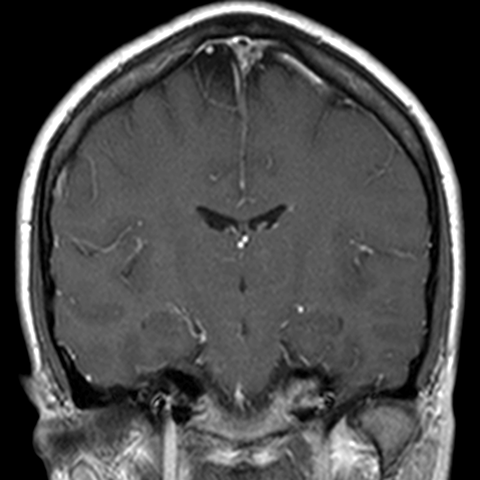

Cranial Meninges (normal) [7 of 8]